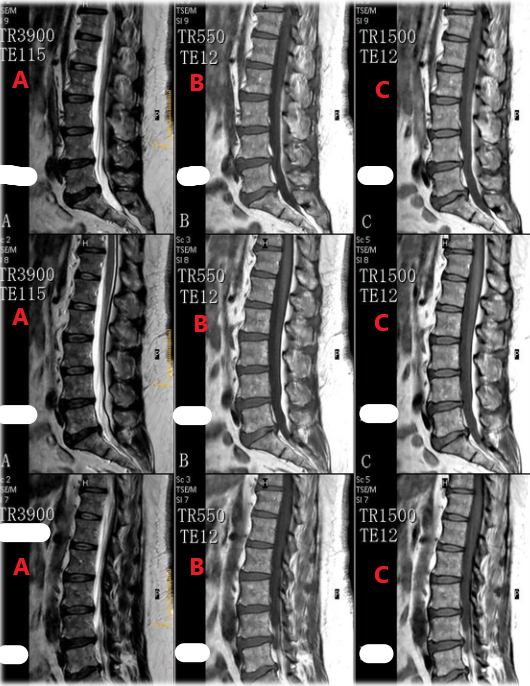

Which row of these images is T2 weighted with fat signal suppressed ?

D

Which row of these images are T2 weighted ?

A

Which row of these images are T1 weighted ?

C